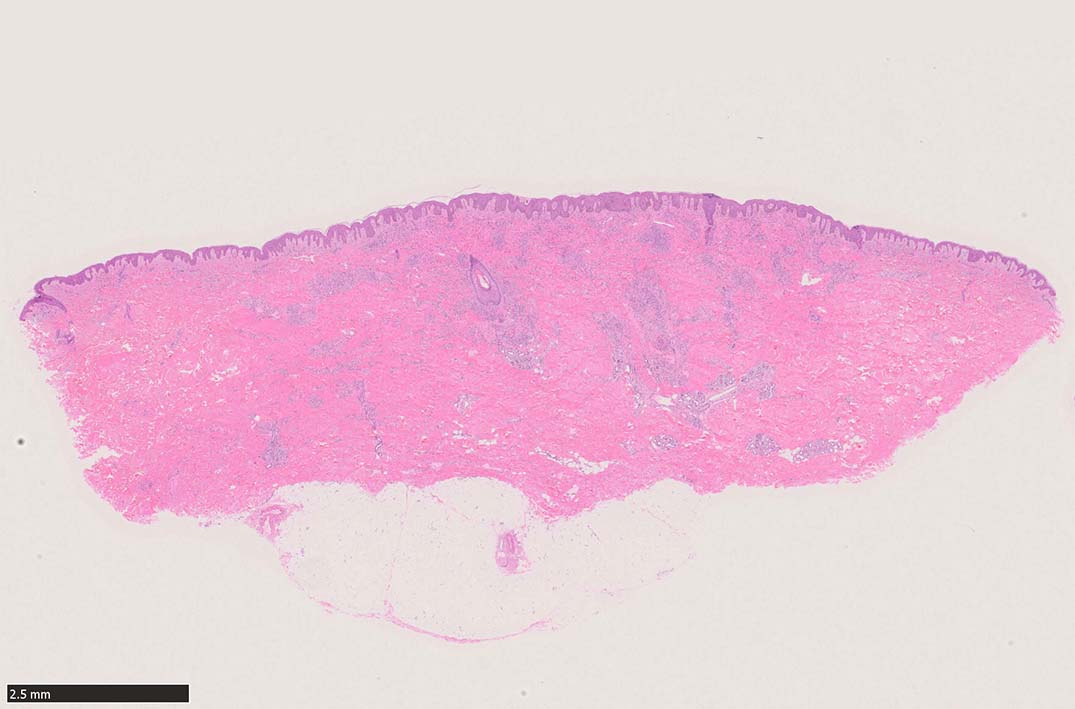

肉眼で平坦な斑状(macule)病変 --> 平板にやや盛り上がった隆起; 局面(plaque)病変 --> 更に進行し結節状(nodule)病変に進行する. (病理所見も病変の進行とともに変化している.)

初期斑状病変の病理

初期の斑状病変の組織学的所見はごく軽度の炎症反応の様相を呈し, 真皮内の正常毛細血管を囲むようにして拡張した血管内皮様細胞による管腔が認められる.

好中球などの炎症細胞浸潤はまれであるが, 形質細胞はしばしば増加している.*5

この時点ではKaposi肉腫特有の線維芽細胞様紡錘形細胞(spindle cells)は少なく, 診断はときに困難である. (HHV-8免疫染色が必須)

30歳代後半 男性. 1ヵ月前から痒みがあった.近医を受診し, 当院を紹介される. 右肩, 左胸部に暗赤色調の軽度隆起を認める. 皮下には腫瘤は触れない(外来担当Drの記載)

細血管周囲に血管内皮様の紡錘形細胞が増生, 一部に赤血球をいれた裂隙の形成がある. 細胞の異型はみられず, mitosisの増多もない. hemosiderin-laden macrophageが散在する.

病変は真皮内に現局している. 初期斑状病変に相当すると考えられる. 本例では, 特徴とされる形質細胞浸潤増加はみられない.